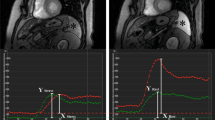

Qualitatively, positive SSO in CMR was defined as a visually perceivable lower splenic enhancement on stress compared to rest first-pass CMR images, as previously reported.9 The visual analysis was performed by two independent readers in a blinded fashion. In the case of disagreement, consensus with a third independent reader was sought. Greyscale values were normalized and identical values were applied to stress and rest images for better comparability.

For quantitative SSO analysis, regions of interest (ROIs) were drawn in the spleen on stress and rest images to generate time–intensity curves using commercially available software (CMR 42 Version 5.9.4, Circle Cardiovascular Imaging, Calgary, Alberta, Canada). Corrected peak signal intensities of the spleen were calculated for stress and rest by subtracting baseline intensity (pre-contrast) from peak intensity after first-pass perfusion. Finally, the splenic intensity ratio (SIR) was calculated by dividing the baseline-corrected peak splenic intensity during stress by the baseline-corrected peak splenic intensity at rest (SIR = (splenic intensityStress−splenic intensityBaseline)/(splenic intensityRest−splenic intensityBaseline)), (Figure 1).

CMR short-axis first-pass perfusion images in a patient undergoing adenosine stress PET/MR with positive SSO (*) defined as visually perceivable lower splenic enhancement on first-pass stress (A) compared to rest (B) perfusion and the corresponding splenic signal intensity curves, showing an SIR of 0.37 (C)